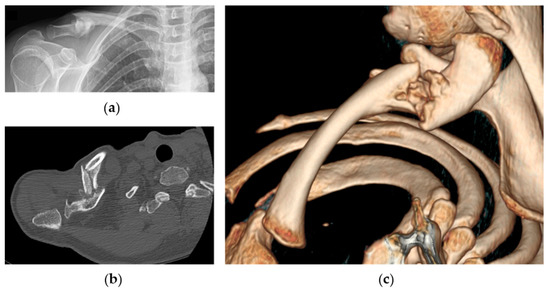

- Biz, C.; Tagliapietra, J.; Angelini, A.; Belluzzi, E.; Pozzuoli, A.; Berizzi, A.; Ruggieri, P. The challenging management of a delayed union midshaft clavicle fracture complicated by an acute pseudoaneurysm of the subclavian artery in a superelderly diabetic patient. Aging Clin. Exp. Res. 2019, 31, 567–569. [Google Scholar] [CrossRef]